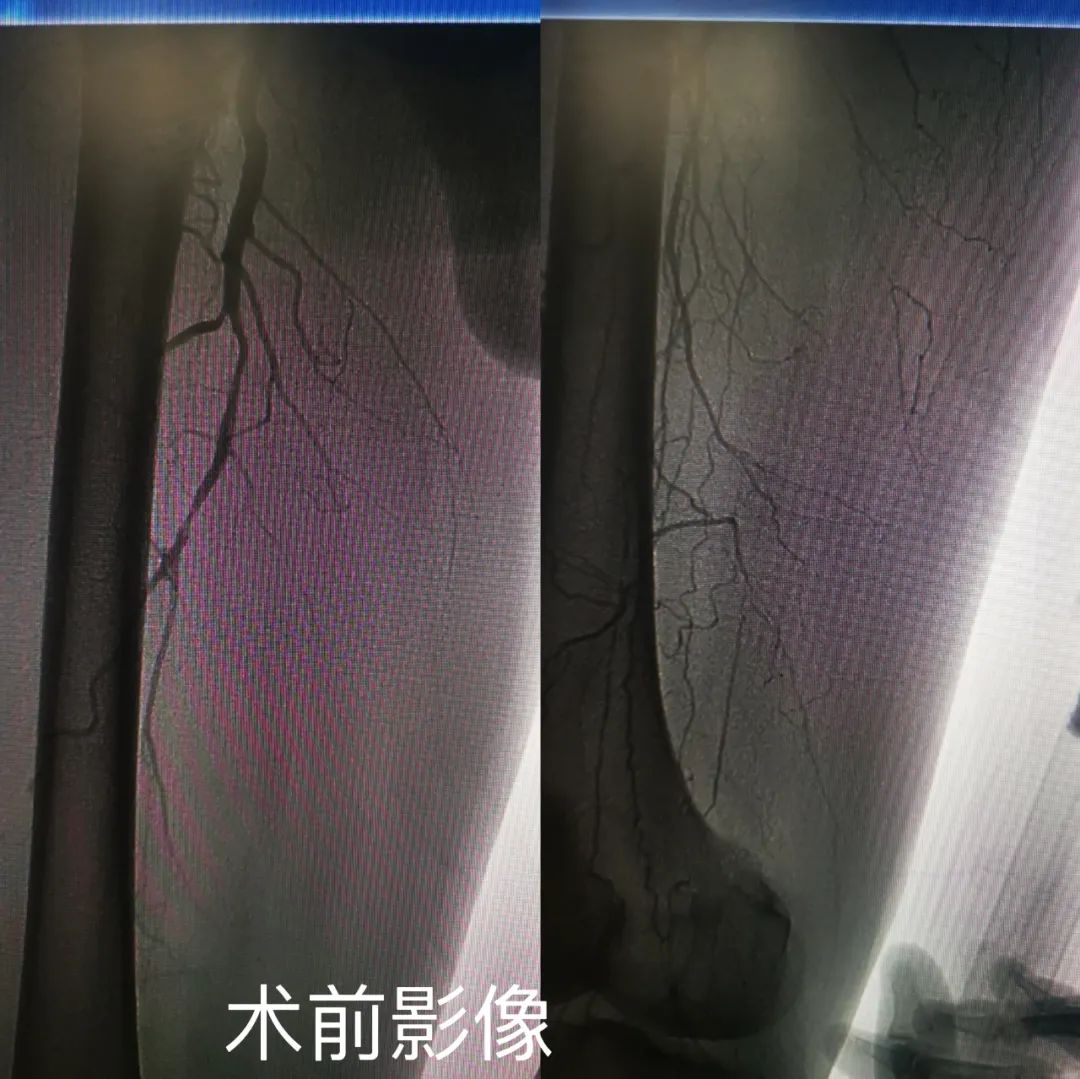

李某,男,81岁,因“右下肢疼痛10余天”入院,既往高血压病史50年,血压控制尚可。入院后行下肢动脉CTA提示右侧股浅动脉、腘动脉闭塞,给予抗凝、抗板治疗,仍有静息痛存在。面对患者高龄且病情重的情况,魏东升主任经术前讨论,考虑到患者为近期(14天以内)血栓形成,若不尽早恢复肢体血流,很容易导致下肢的缺血坏死,甚至可能面临截肢的风险,需尽早进行手术。经术前讨论后,预行下肢动脉球囊扩张、下肢动脉内血栓旋切术。应用Rotarex血栓抽吸减容系统,以40000转/分钟钻头将血栓切碎,同时将其抽吸出体外。术毕患者右下肢皮温良好,患者自觉症状明显缓解,此例手术过程中未植入支架,符合DCB血管治疗时代的“leave nothing behind”理念。可最大限度避免术后并发症的出现。经术后随访患者恢复良好,无间歇性跛行、无静息痛,症状明显缓解。